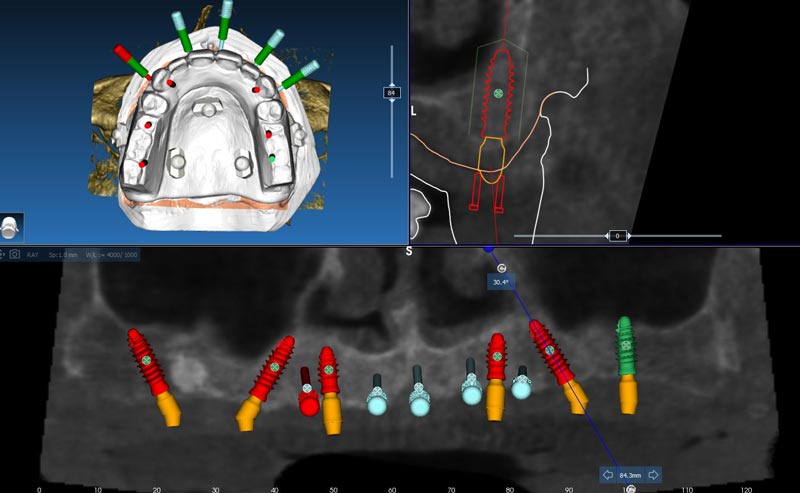

Pianificazione implantare al software Real-Guide

Pianificazione implantare in trasparenza

Studio del taglio, adattamento del mascellare alla pianificazione implantare, anche in armonia della pianificazione protesica

Taglio per resettiva previsto

Visione del mascellare con resettiva effettuato, e progettazione protesica